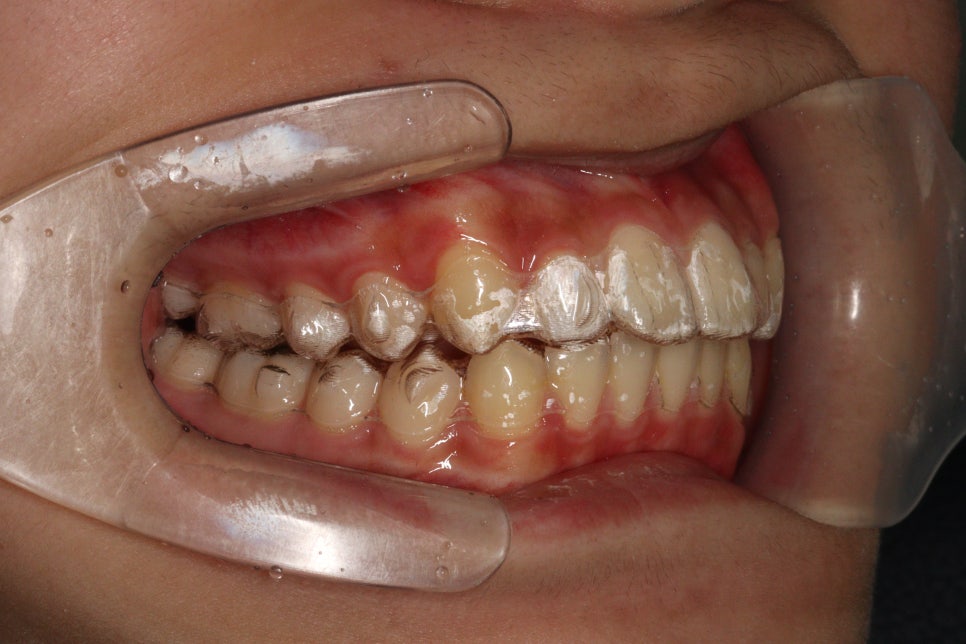

이 아이는 앞니 두개가 튀어나온 것을 고치고 싶어했습니다.

치료 전과 후 입니다.

앞니가 후방이동 한것이 확인됩니다.

우리는 부분교정을 한것이 아니라 간단한 전체교정을 한것입니다.